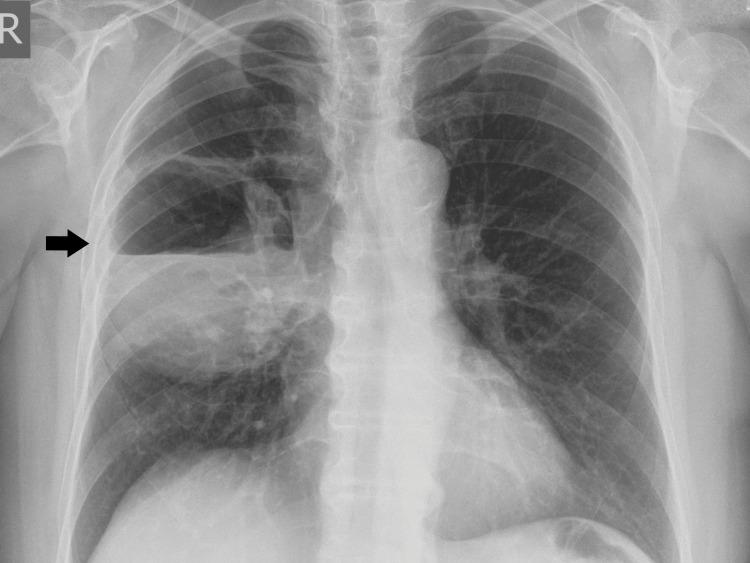

巨大坏疽性肺脓肿一例罕见病例。

A Rare Case of Giant Gangrenous Lung Abscess.

Gangrenous lung abscess (LA) is a limited form of lung gangrene. Although its frequency has decreased dramatically in recent years, it occupies an important place in clinical practice. Delaying its diagnosis or incorrect treatment leads to a risk to the patient's life. Timely diagnostics and treatment reduce morbidity and mortality rates. А 68-year-old woman who underwent a right upper bilobectomy for a gangrenous LA is presented. The case is considered in the context of the prolonged therapeutic course and the need for surgical treatment.

摘要

坏疽性肺脓肿(LA)是肺坏疽的一种局限形式。尽管近年来其发病率已大幅下降,但在临床实践中仍占有重要地位。延误诊断或治疗不当会危及患者生命。及时诊断和治疗可降低发病率和死亡率。本文介绍了一名68岁因坏疽性肺脓肿接受右上叶双肺叶切除术的女性患者。结合其漫长的治疗过程和手术治疗的必要性对该病例进行了分析。